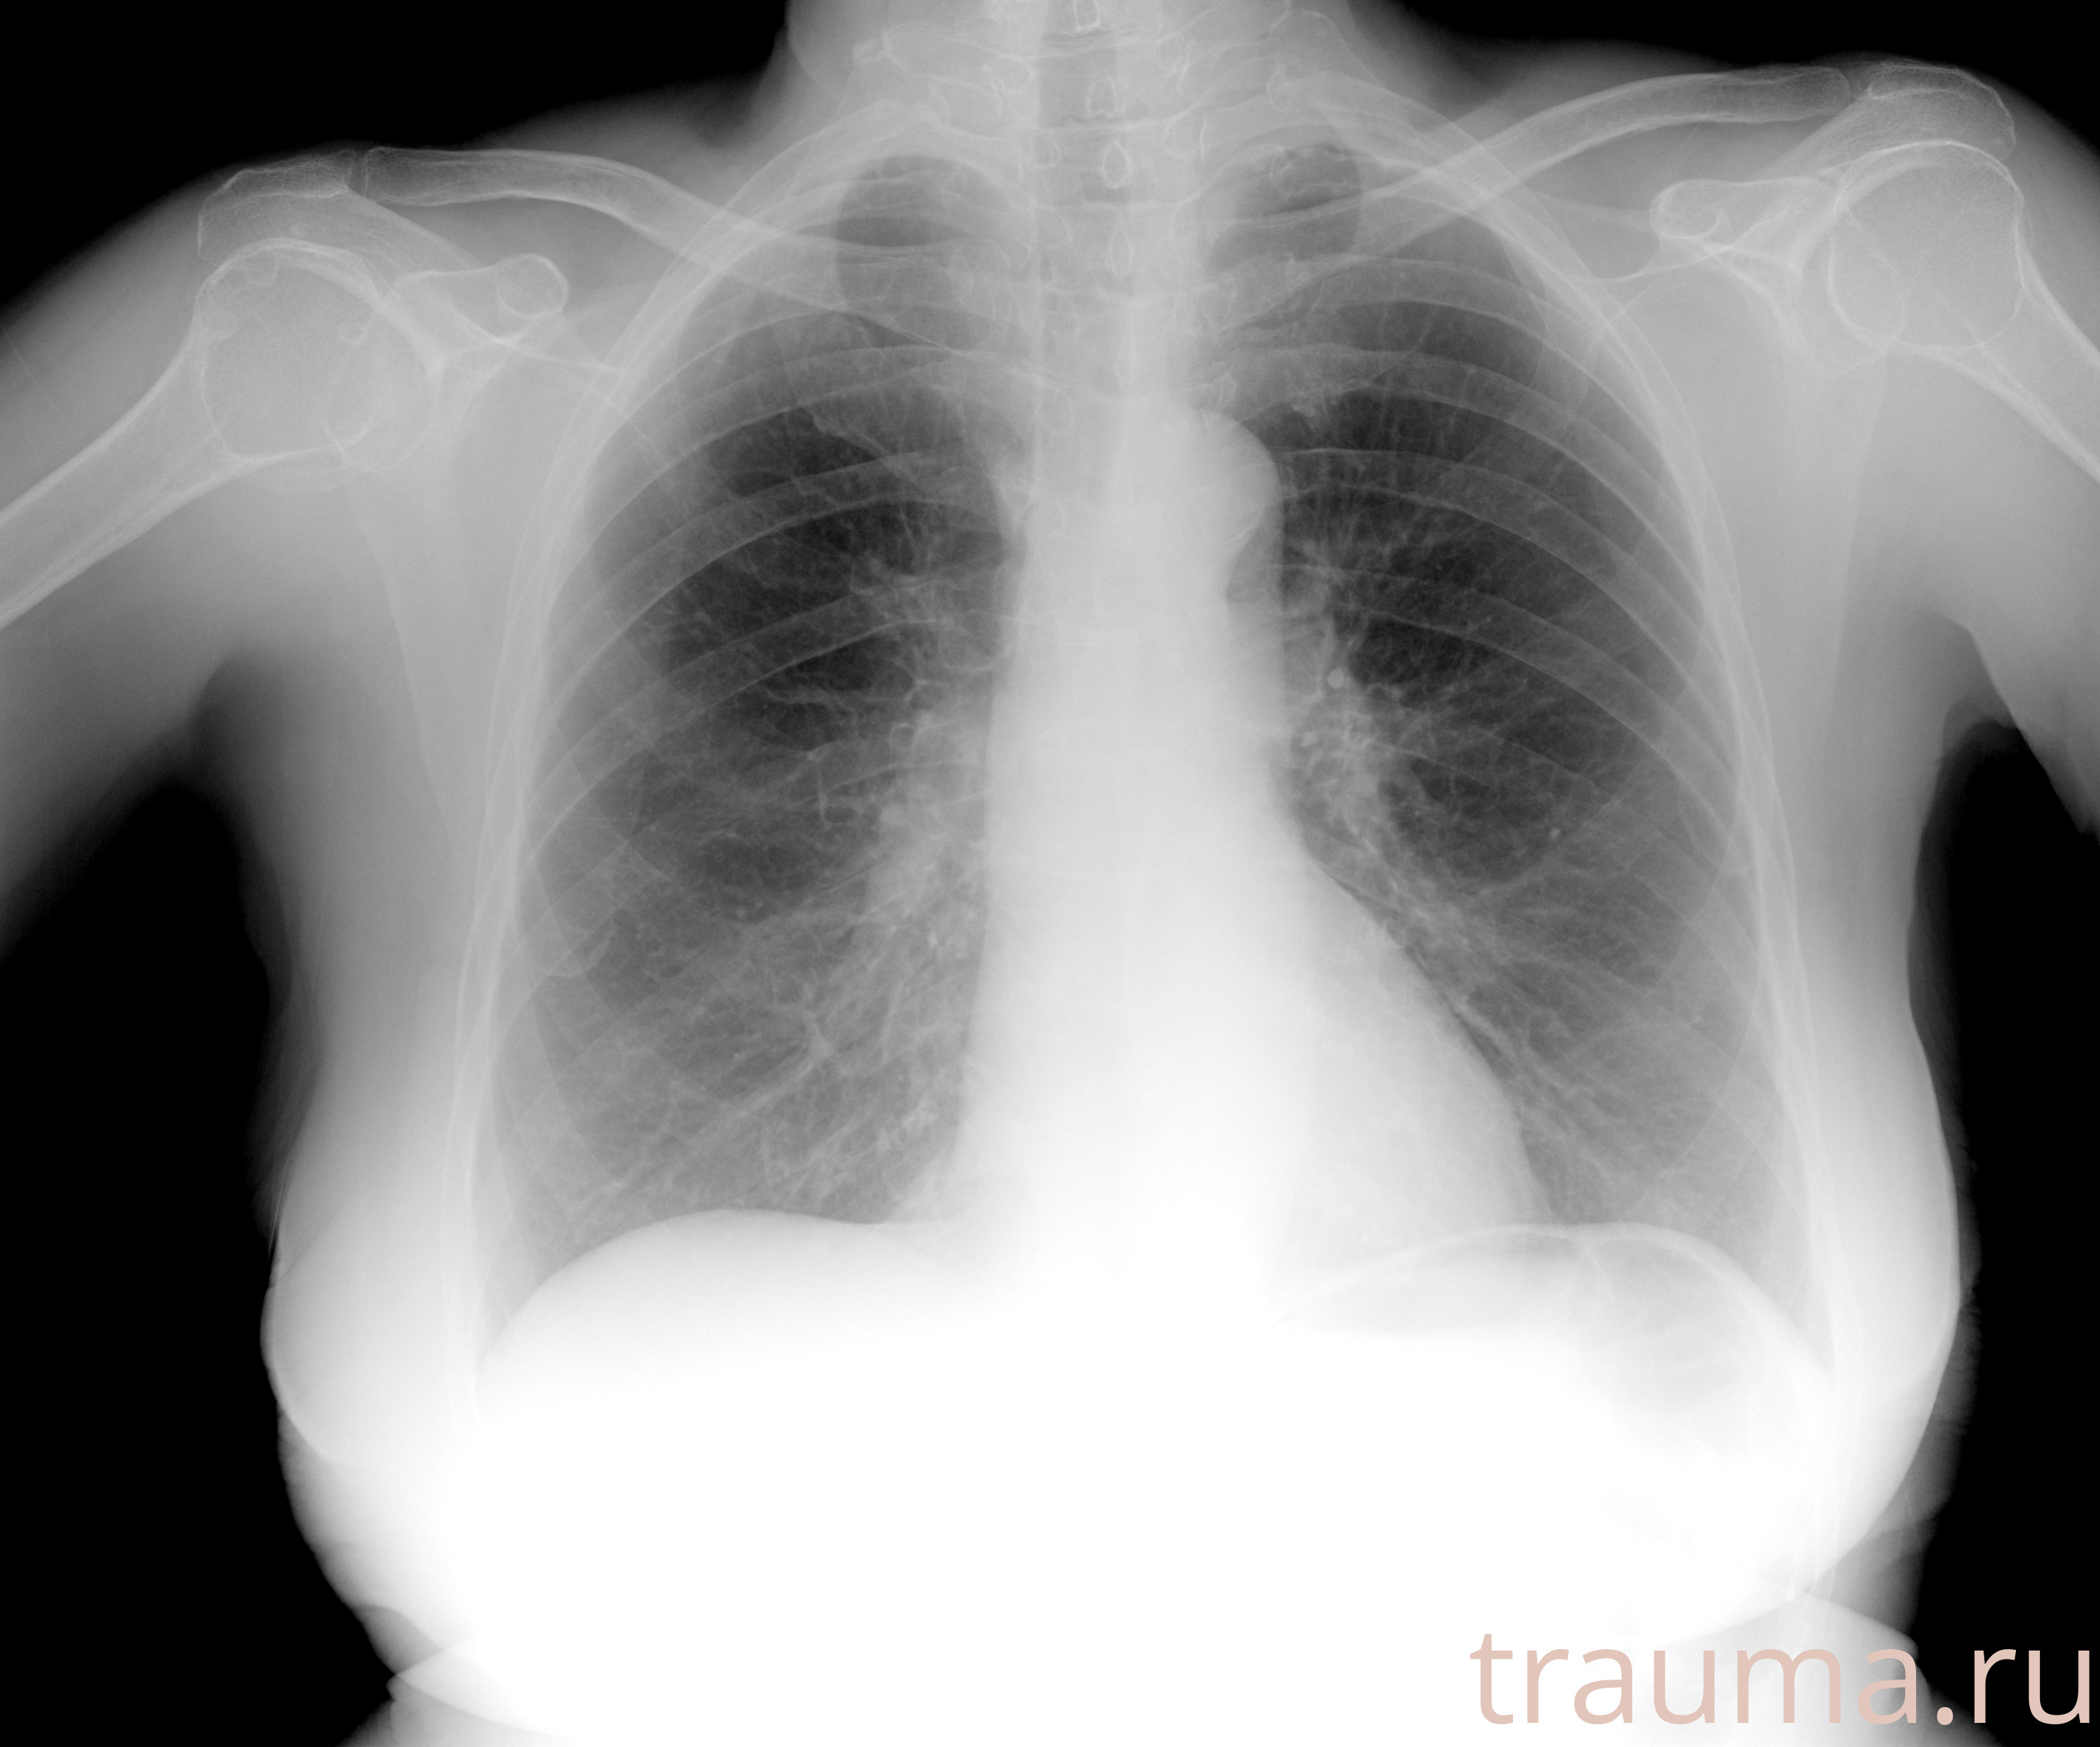

Рентген на дому: по вашему адресу приезжает врач-рентгенолог, травматолог-ортопед с мобильным рентгеновским аппаратом, проводит диагностику травмы или заболевания, делает необходимые рентгенограммы, дает рекомендации по дальнейшему лечению. Получить качественные снимки в домашних условиях возможно благодаря уникальной методике, разработанной МосРентген Центром для института  Склифосовского

при переломе шейки бедра и пневмонии от компании МосРентген Центр - партнера Института имени Склифосовского